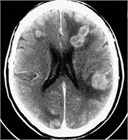

1. 単発・少数転移例では、3 cm以上の大きさの腫瘍に対しては、分割定位放射線照射も行われるが、放射線壊死のリスクも高くなるため、全身状態が安定している患者に対しては手術が第1選択で行われる(推奨度2)。2 cm以上で、症候性でmass effectがあれば手術適応としてもよい。